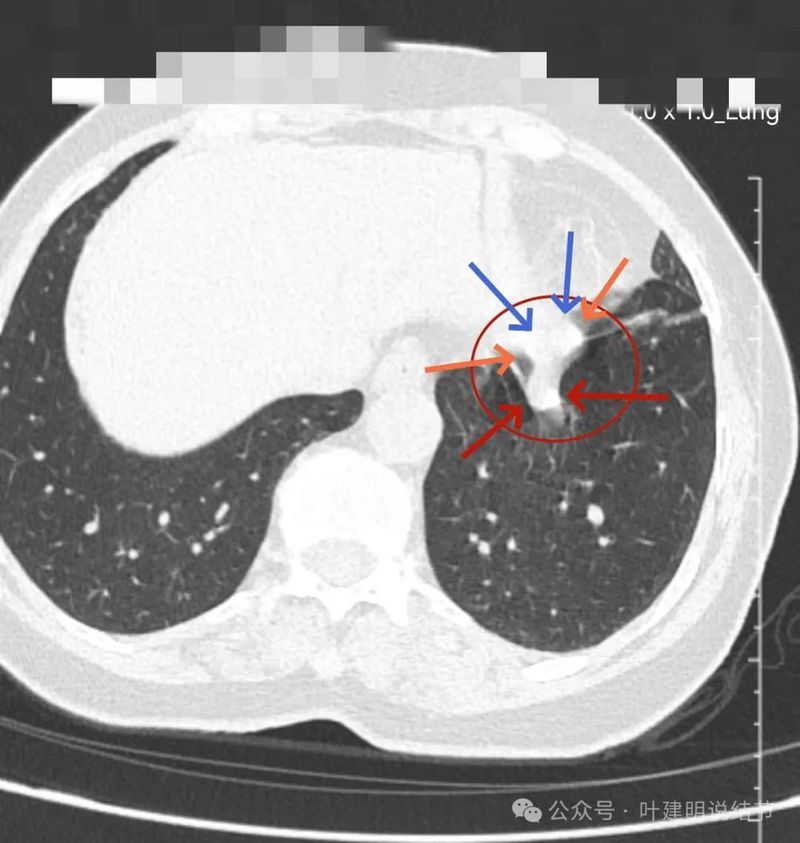

左下实性结节,明显有膨胀感,边缘虽然光滑,但给人感觉不舒服,恶性的可能性大些。

轴位病灶实性,分叶,膨胀!

病灶表面不平,有浅分叶,与膈肌之间有间隙。

与膈肌之间间隙明显,病灶实性,膨胀性明显,边缘相对较为光滑。

病灶浅分叶,膨胀性,周围有很淡的磨玻璃密度似的,这可能是检查时屏气屏得不太好的关系,不太符合混合磨玻璃结节的样子。

整体感觉较圆,膨胀性是明显的。膈肌有点被它顶过去的样子。

上图层面相对最大,感觉鼓鼓的。

边界与轮廓清。

上图显得膨胀感欠了点,但分叶与表面不平是明显的。